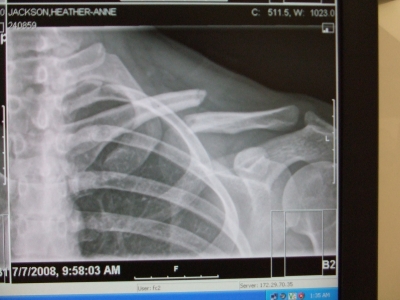

X rays from July 7th, 2008. 1 month after the initial break.